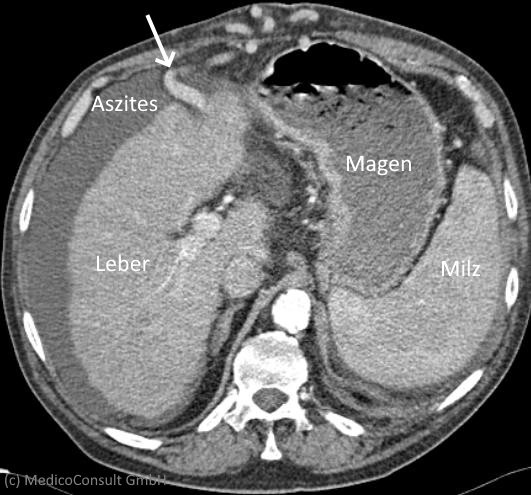

Computertomographie

Computertomographisch lassen sich eine fortgeschrittene Leberzirrhose und ein Pfortaderhochdruck (portale Hypertension) meist gut erkennen. Die Computertomographie (CT) dient vor allem der Suche nach Komplikationen, so der Suche nach Leberkrebs (hepatozelluläres Karzinom, HCC). Denn jede Leberzirrhose bedeutet ein deutlich erhöhtes HCC-Risiko. In diesen CT-Schnitten wird eine vergrößerte Leber mit Zirrhose dargestellt, die zu einer portalen Hypertension mit gestauter Milzvene (2 Sternchen) und einer Milzvergrößerung (Splenomegalie) geführt hat (Abb1: Milz *, Milzvene **, Bauchspeicheldrüse ***, Abb2: Leber X, Milz XX).